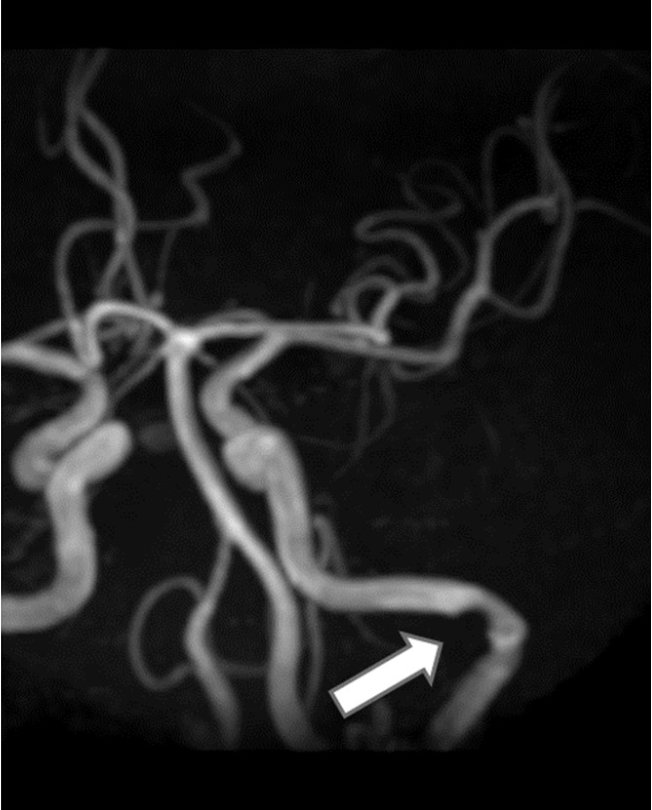

3D TOF-MRA MIP画像の内頚動脈の信号欠損(矢印)に関して血管狭窄以外に考えられる影響はどれか.(正解2つ)

- 乱流

- 飽和効果

- 位相分散

- MTC効果

- In-flow 効果

TEを短くすると位相分散の影響を小さくすることが出来て、乱流の影響を抑えることが出来る

解説

- 正しい

- 間違い